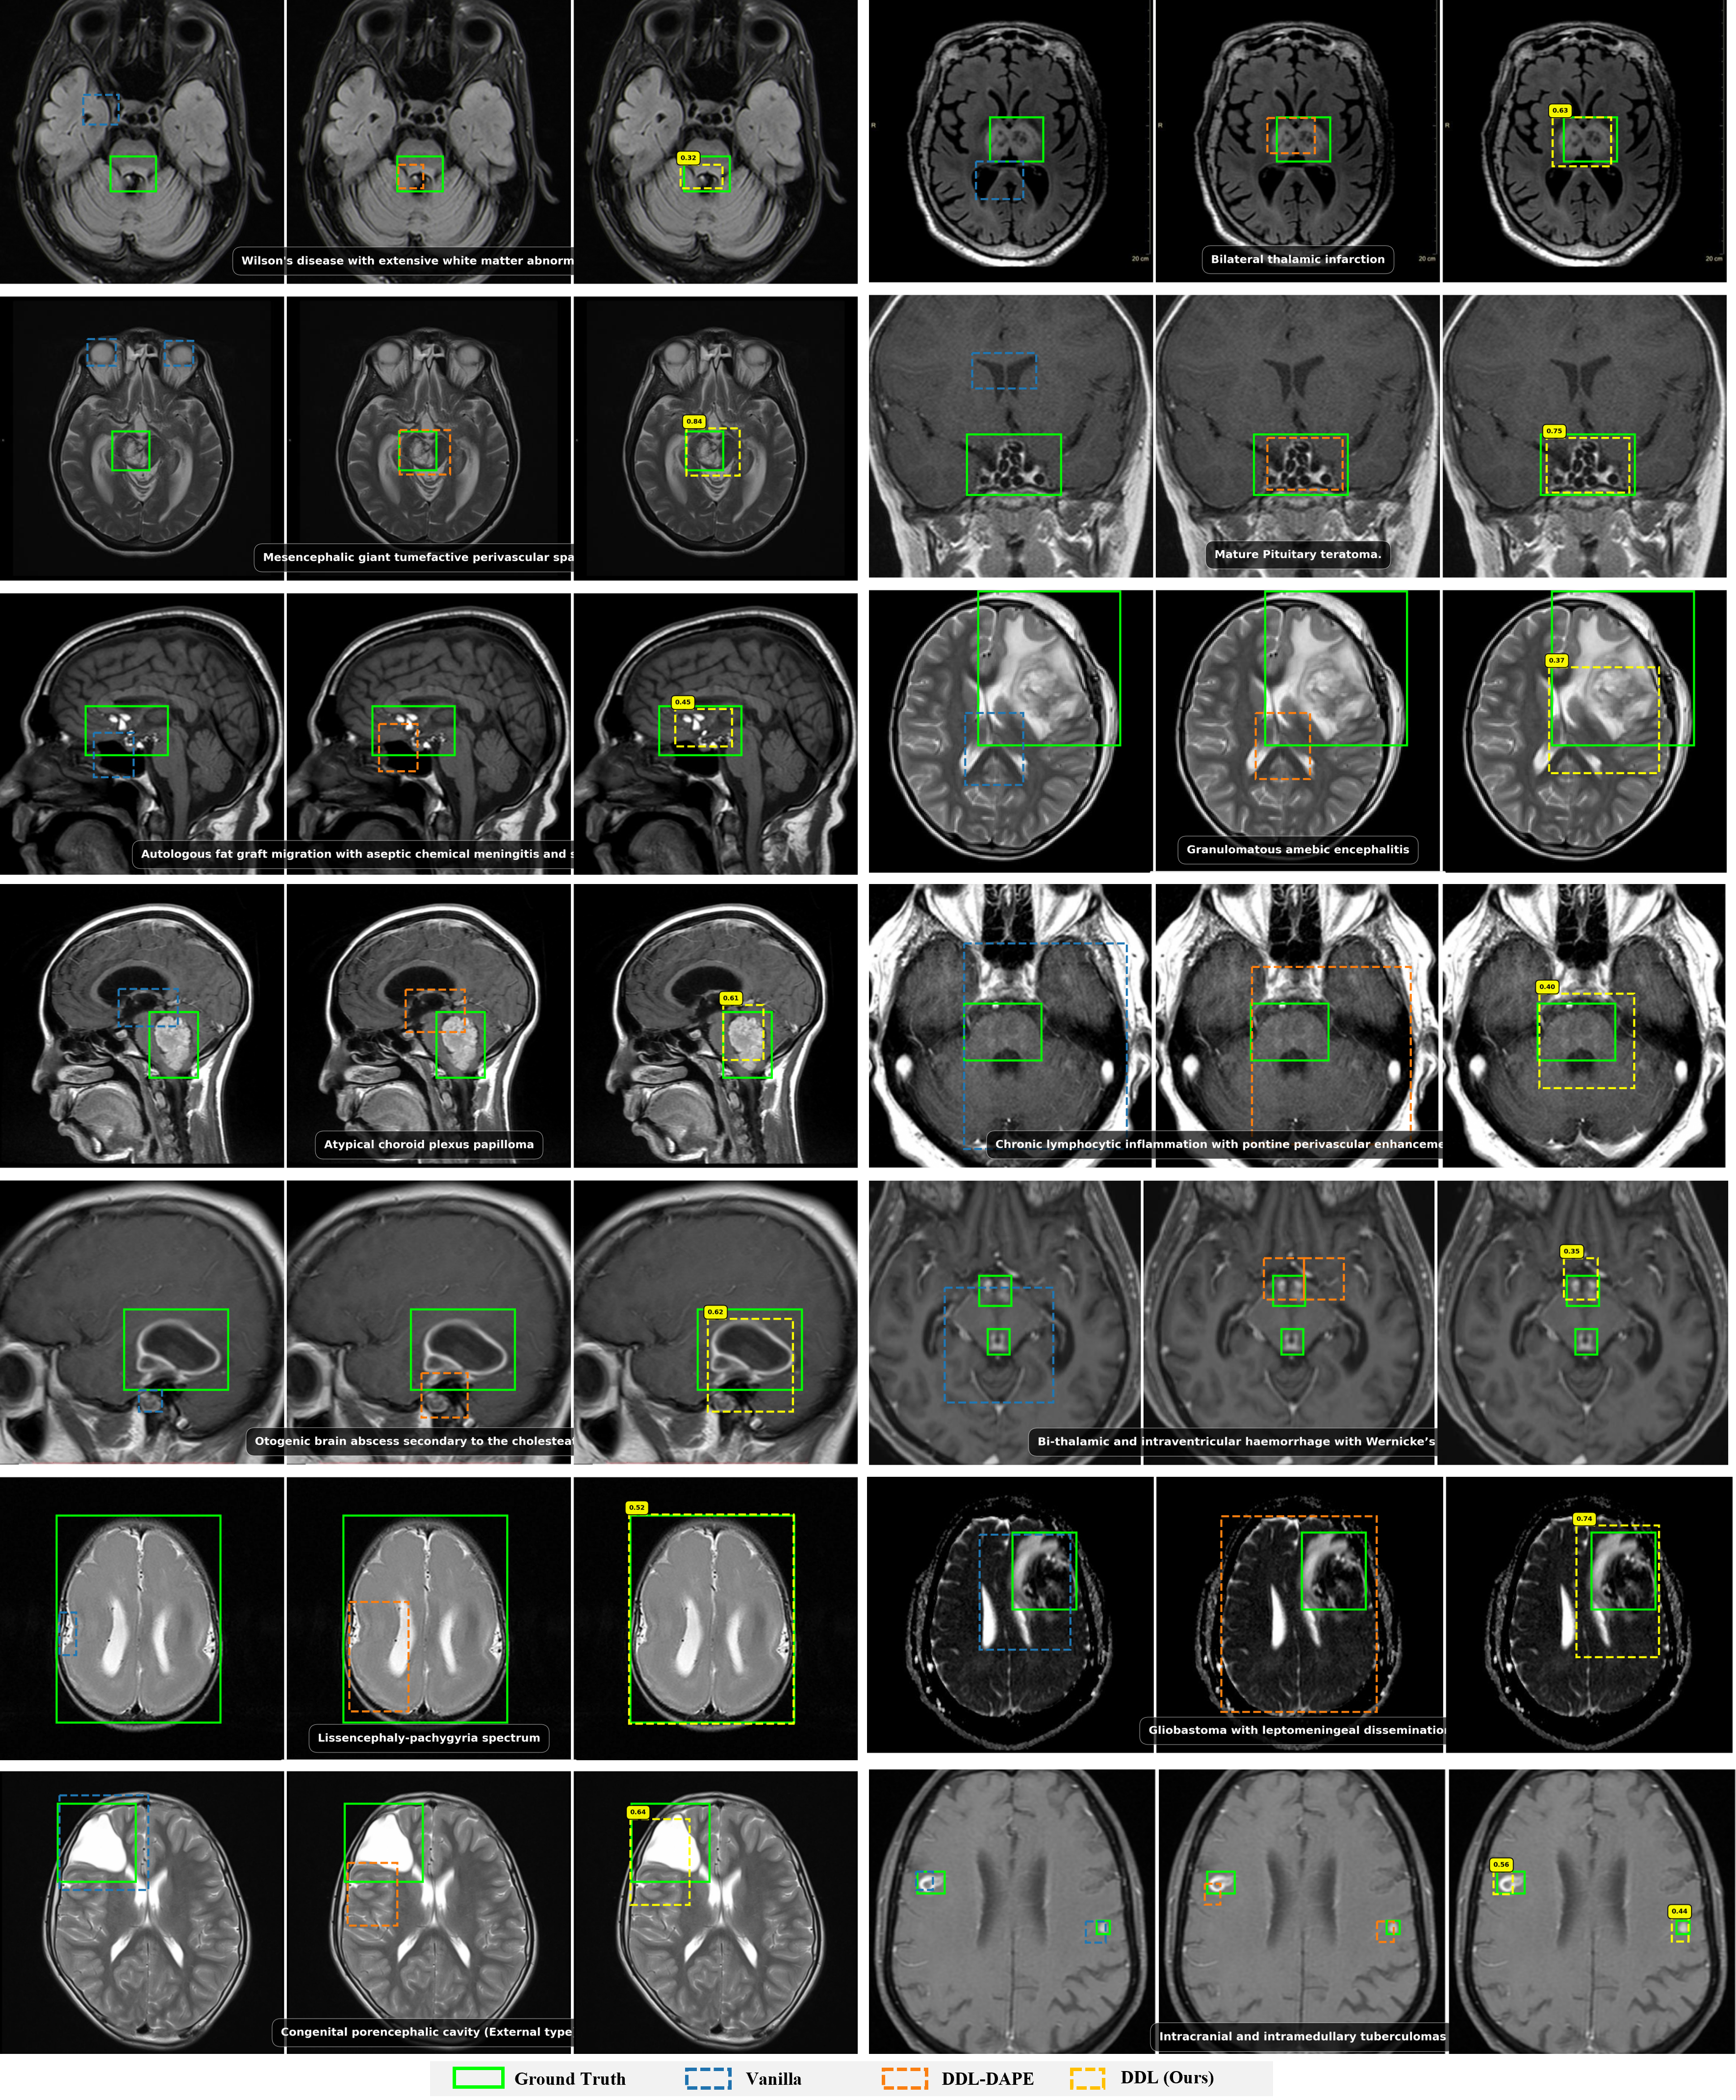

72B Results

Qwen2.5-VL-72B Grounding Performance